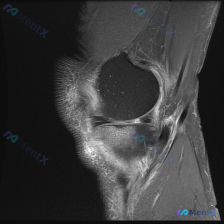

病例读片分享:临床怀疑半月板异常,MRI却只看到髌周病变 基本影像信息 提供的影像为膝盖MRI-T2序列矢状位,切面位于膝关节前部髌股关节区域,图像存在一定截断伪影,未显示后交叉韧带及大部分后侧软组织结构。 影像核心发现 整理一下客观观察到的异常: 1. 髌前皮下软组织水肿:髌骨前方及皮下组织层可见...